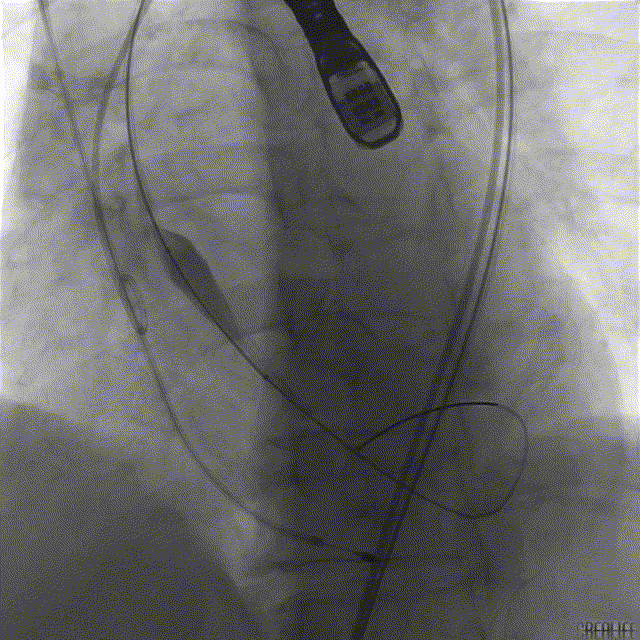

手术过程概览:

TaurusOne® 输送器顺畅过弓

造影辅助定位

精准释放

术后即时评估,患者超声下指标改善明显,无明显瓣周漏、瓣中漏;造影示瓣膜工作形态良好,无明显反流。